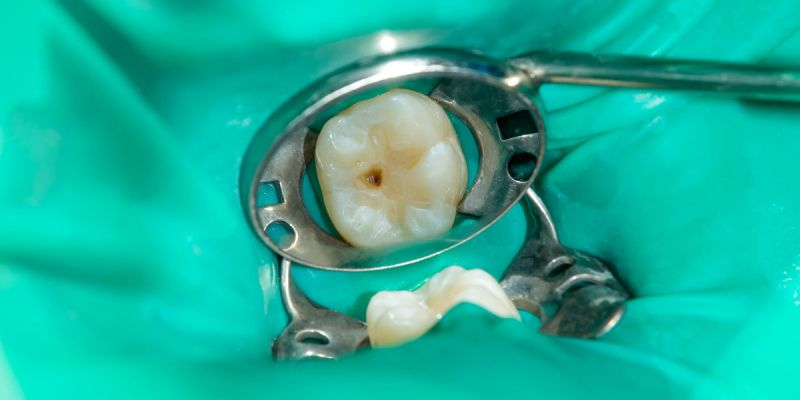

- Механизм действия аппарата Вектор заключается в использовании энергии ультразвука и совместной подаче особой суспензии гидроксиаппатита (Vector Fluid polish).

- При работе используют специальные насадки, выбор которых обусловлен глубиной и объемом кармана.

- Терапевтический эффект достигается за счет удаления всех отложений в пародонтальном кармане, включая грануляции и биопленку. Полируется поверхность корня, что создает долговременные условия для отсутствия рецидивов заболеваний. В результате в тканях пародонта создаются предпосылки для регенерации (заживления).